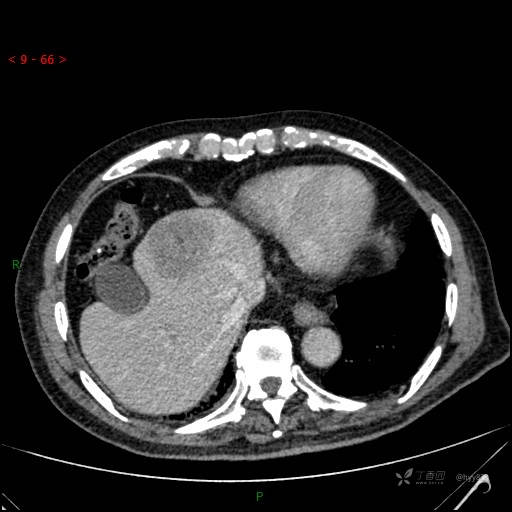

肝脏CT平扫

img